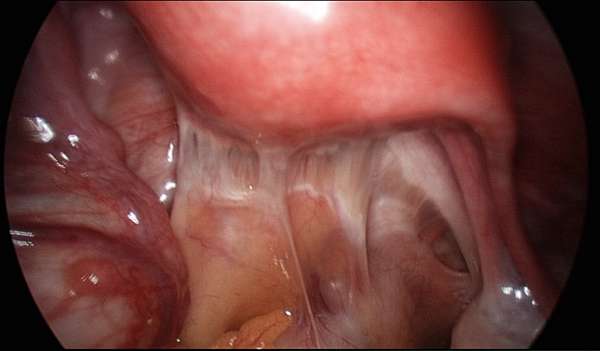

因為五十肩而動手術的人數其實不多醫師建議這樣治療 骨科 復健 科別 元氣網

手術